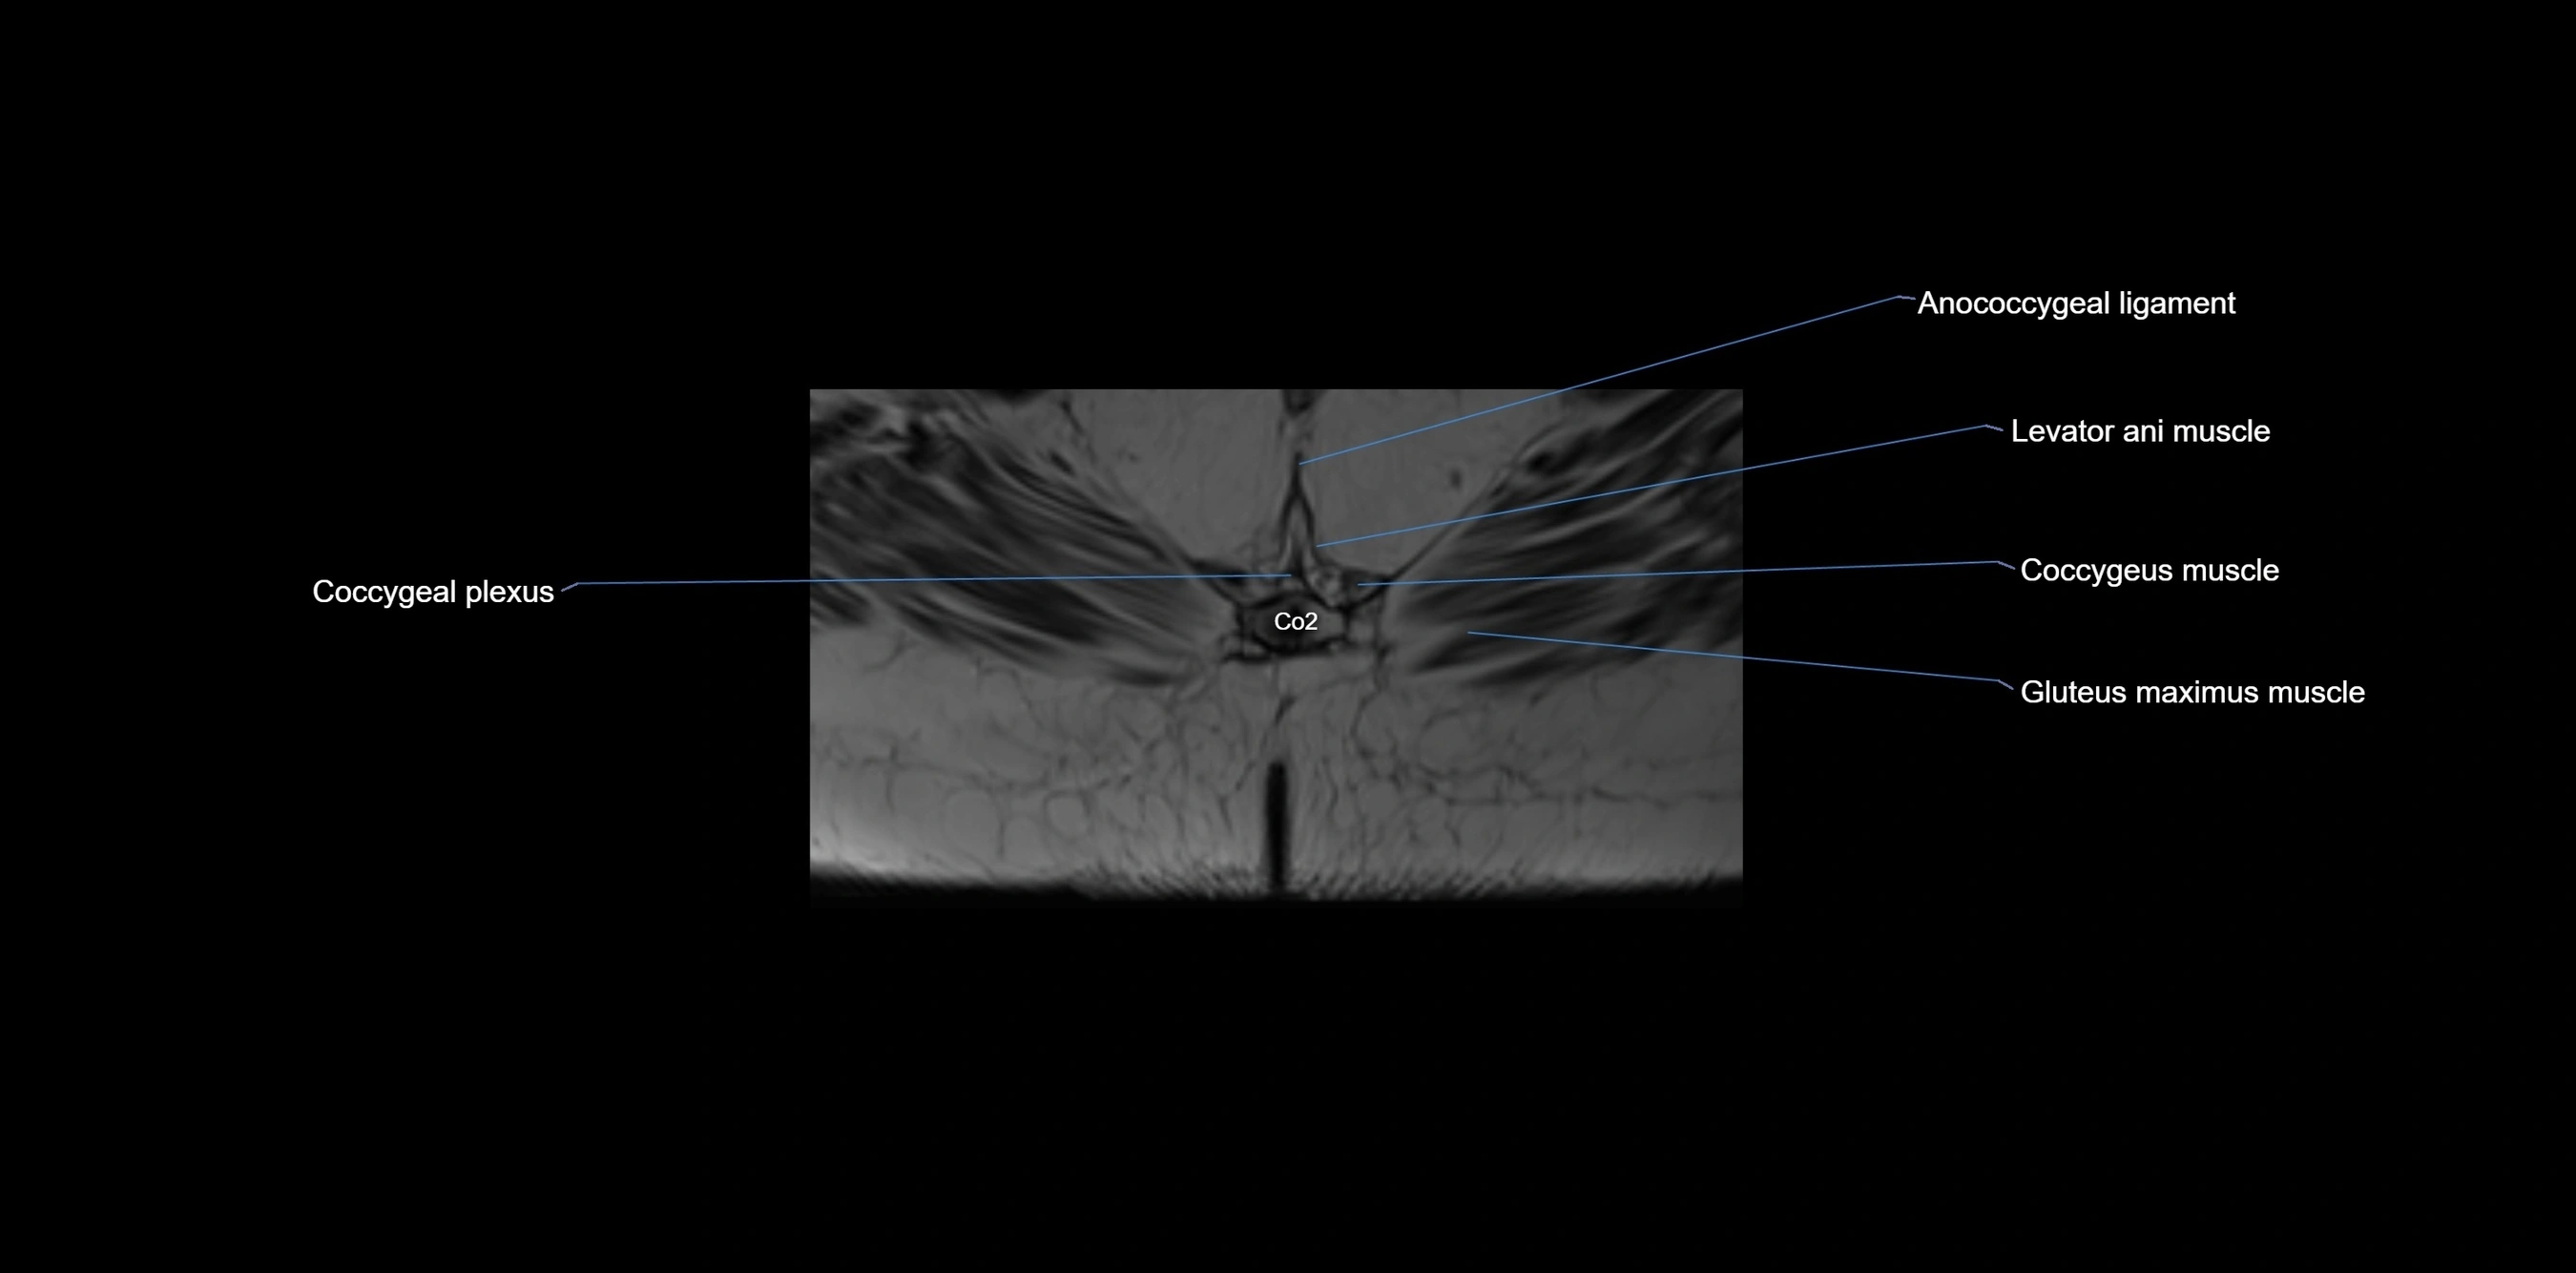

CT image

image